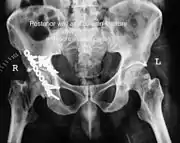

| Acetabular fracture as seen on plain X-ray |

To understand the fracture pattern of a fractured acetabulum, it is essential to have minimum three x-ray views, though use of CT scan with 3-D reconstruction of images has made understanding of these fractures easier.

- Pelvis with both hips antero posterior view. This view shows six important landmarks of the acetabulum, specifically:

- Weight bearing dome